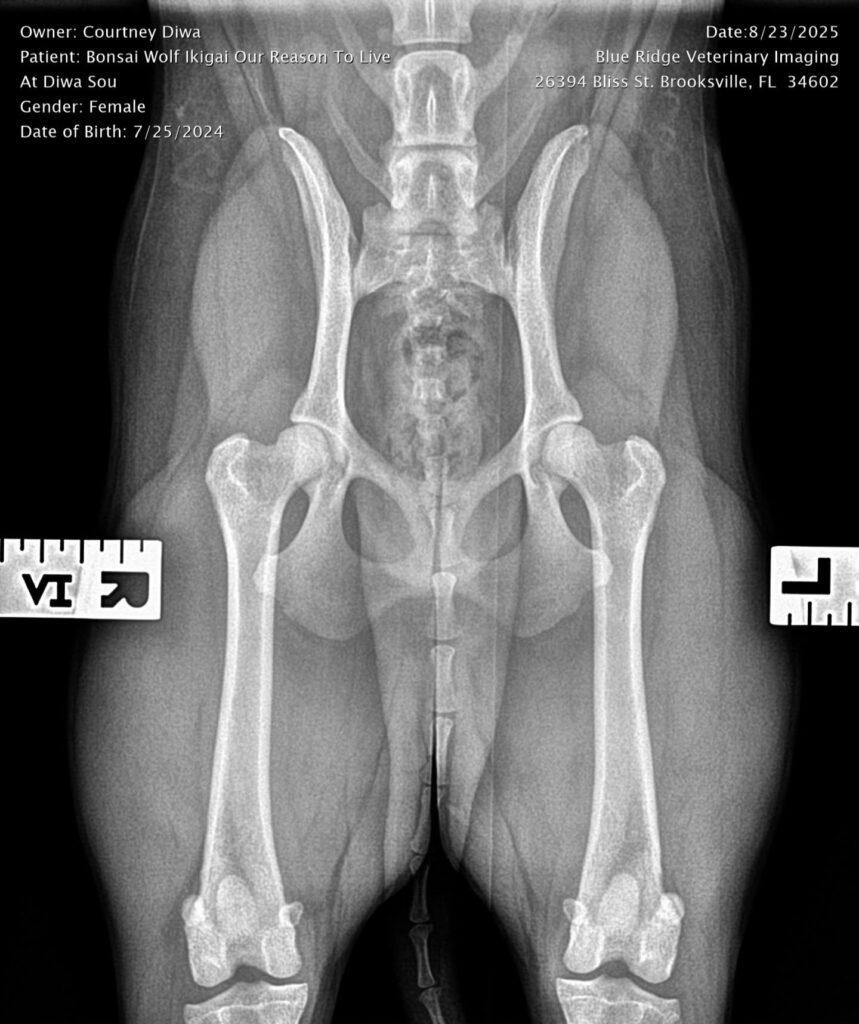

Titles & Health Certificates